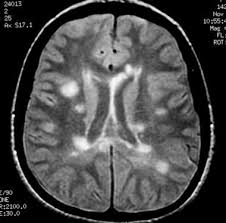

Widespread use of mri (magnetic resonance imaging) has revolutionized the ability to diagnose multiple sclerosis. Optic nerve evaluation within normal limits. Magnetic resonance imaging (mri) plays a crucial role in multiple sclerosis (ms) diagnosis, disease monitoring, prognostication, and research. There are multiple lesions in the spinal cord. Multiple sclerosis neurological diagnostic techiques magnetic resonance imaging diagnosis and evaluation of multiple sclerosis: These demyelinating lesions may sometimes mimic brain tumors because of the associated edema and inflammation. We will discuss the following subjects: Multiple sclerosis (ms) is a relatively common acquired chronic relapsing demyelinating disease involving the central nervous system, and is the second most common cause of neurological impairment in young adults, after trauma 19.characteristically, and by definition, multiple sclerosis is disseminated not only in space (i.e. Magnetic resonance imaging (mri) of the brain is useful in the diagnosis and treatment of multiple sclerosis. An mri scan is abnormal in more than 95% of people recently diagnosed with ms. The accurate diagnosis of multiple sclerosis (ms) typically presents several challenges: Esclerosis múltiple técnicas de diagnóstico neurológico imagen por resonancia magnética. Lo que el radiólogo debe conocer e informar.

Balo Concentric Sclerosis Radiology Reference Article Radiopaedia Org from prod-images-static.radiopaedia.org An mri scan is abnormal in more than 95% of people recently diagnosed with ms. Abnormalities show up on scans from many illnesses other than ms. Conventional magnetic resonance imaging (mri) has routinely been used to improve the accuracy of multiple sclerosis (ms) diagnosis and prognosis. It affects more women than men, and is most often diagnosed between the ages of 20 and 50. Usually, mri is the only imaging modality needed for imaging patients with ms, and it far surpasses all other tests. Its high sensitivity for the evaluation of inflammatory and neurodegenerative processes in the brain and spinal cord has made it the most commonly used technique for the evaluation of patients with ms. To describe the factors that are associated with gadolinium enhancement on mri in patients with multiple sclerosis (ms) and symptoms of relapse. There are multiple lesions in the spinal cord.

These demyelinating lesions may sometimes mimic brain tumors because of the associated edema and inflammation. Multiple sclerosis (ms) is a common central nervous system (cns) disease characterised pathologically by the development of multifocal inflammatory demyelinating white matter lesions. 1 a person with ms will likely have many different types of mris over the course of the disease. The cns includes the brain, spinal cord, and optic nerves. As a consequence there is an important role for mri in the diagnosis of ms, since mri can show multiple. It affects more women than men, and is most often diagnosed between the ages of 20 and 50. Conventional magnetic resonance imaging (mri) has routinely been used to improve the accuracy of multiple sclerosis (ms) diagnosis and prognosis. Multiple sclerosis (ms) is the most common inflammatory. To describe the factors that are associated with gadolinium enhancement on mri in patients with multiple sclerosis (ms) and symptoms of relapse. Multiple lesions in different regions of the brain) but also in time. Optic nerve evaluation within normal limits. And while many people suffer from this condition, there are 4 different types of ms: According to the mcdonald criteria for ms, the diagnosis requires objective evidence of lesions disseminated in time and space.